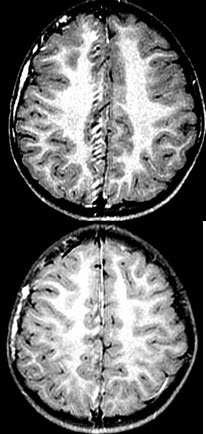

4岁小男孩,右侧颜面部有紫红色瘤,智力障碍,MR检查如图,请选择最可能的诊断( )

A:神经纤维瘤

B:结节性硬化

C:脑颜面血管瘤病

D:脑皮质发育异常

E:脑灰质异位